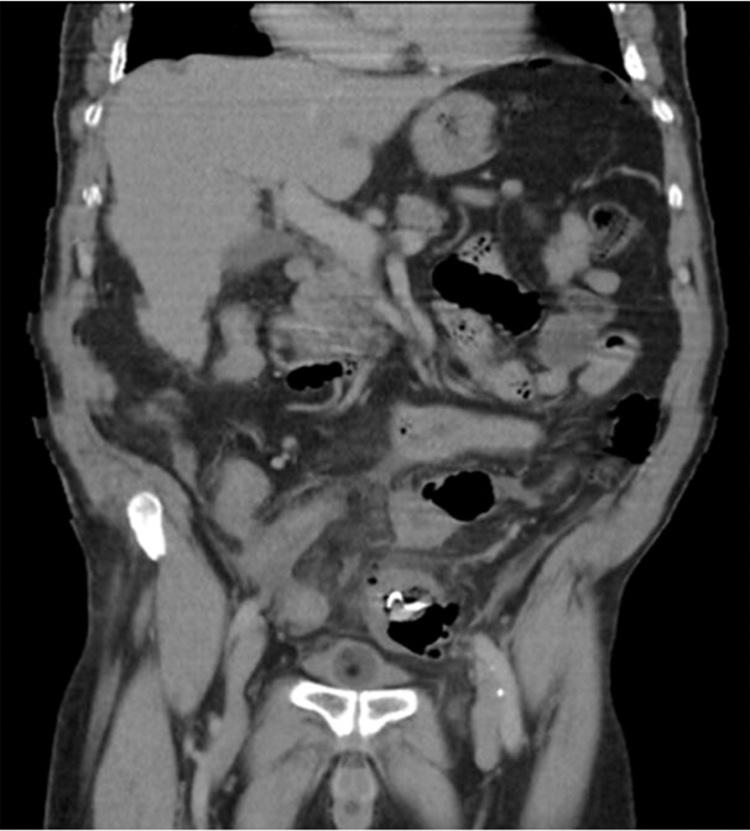

Rare case of an elderly male presenting to the emergency department with an acute abdomen few days post accidental ingestion of his dentures. A detailed history along with a CT abdomen showed perforation in the sigmoid colon adjacent to the site of the swallowed denture.

一名老年男性在意外吞食假牙几天后因急腹症就诊于急诊科,这种情况较为罕见。详细病史及腹部CT显示,乙状结肠在吞食假牙部位附近出现穿孔。